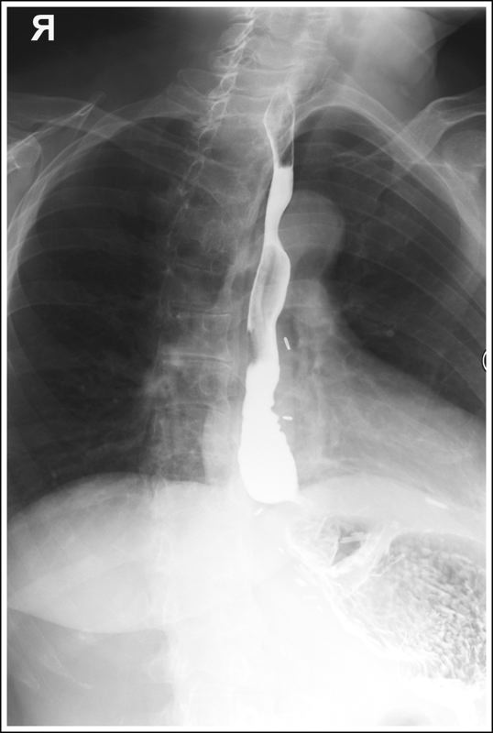

RAO Esophagus with proper positioning

RAO Esophagus with superior and inferior no barium

RAO Esophagus with rotation less than 35-40 degrees